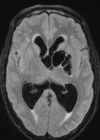

Q

A

Esclerose mesial temporal

Observe a perda de volume, que indica atrofia e causa aumento secundário do corno temporal do ventrículo lateral.

O sinal alto no hipocampo reflete a gliose.

Atrofia hipocampal e hipersinal T2. Cerca de 10% dos casos são bilaterais (dificulta o diagnóstico). A etiologia é desconhecida, mas há uma relação entre STM e convulsões febris prolongadas no início da vida A esclerose mesial temporal pode ocorrer em associação com outras patologias, principalmente displasia cortical focal (dual pathology).

203